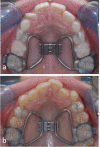

Objective: Rapid maxillary expansion (RME) is an established and frequently used procedure to overcome maxillary constriction. In-depth studies about morphological changes of the alveolar process and its immediate surroundings are missing. Therefore, the aim of the present study was to examine the treatment effects of a dentally anchored, rapid maxillary expander at different dentition stages upon palatal width, height and shape.

Material and methods: The dental casts of 114 patients-taken immediately before and after RME-were three-dimensionally analysed. Depending on the dentition stage, the patients were divided into two groups (each n = 57, group 1, early mixed dentition; group 2, late mixed or permanent dentition).